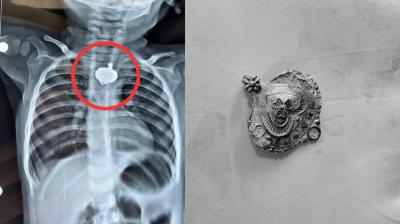

बड़वानी में 9 माह के बच्चे की आहार नली में फंसा मंगलसूत्र, डेढ़ महीने बाद एक्स-रे से खुलासा

24 Nov, 2025 08:30 AM IST | SAMACHARPRIME24.COM

बड़वानी: रविवार को जिला अस्पताल में एक बेहद संवेदनशील और हैरान करने वाला मामला सामने आया. जब 9 माह के एक बच्चे के गले में मंगलसूत्र फंसा हुआ देखा गया. घटना...